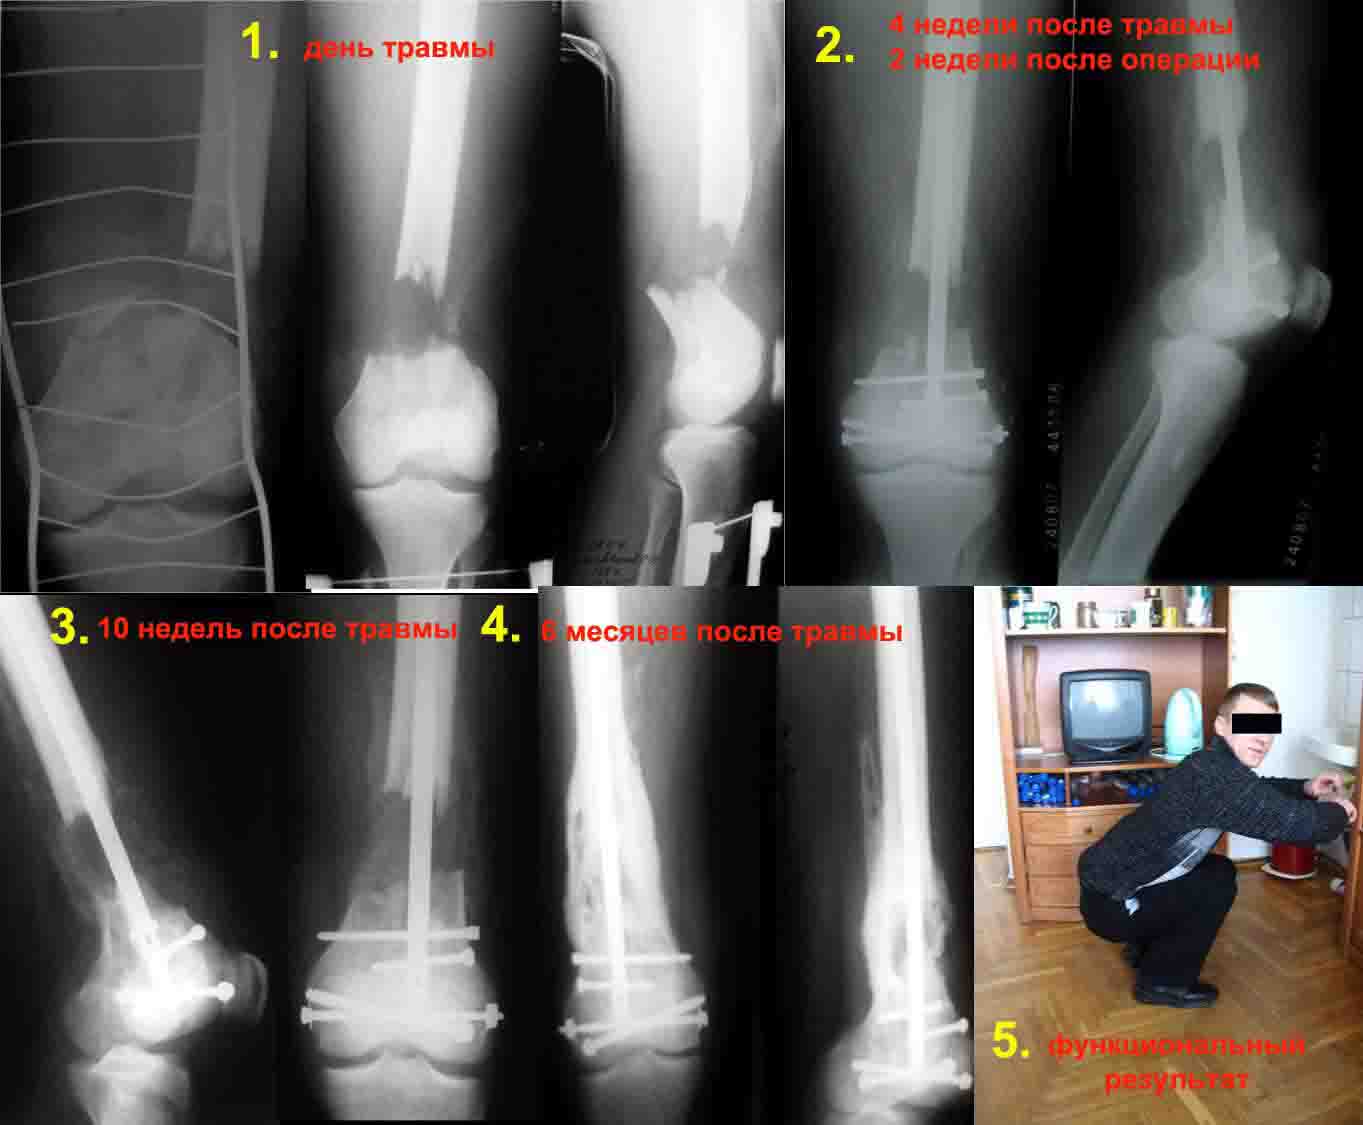

1. Открытый с дефектом кости 5 см оскольчатый внутрисуставной перелом дистального эпиметафиза бедренной кости. Величина дефекта установлена после сравнительных рентгенограмм обоих бёдер с линейкой. При поступлении выполнена ПХО раны, скелетное вытяжение за бугристость большеберцовой кости.

2. После долгих сомнений выполнена открытая репозиция перелома эпифиза бедренной кости, закрытый блокированный интрамедуллярный остеосинтез (к слову, оперативное вмешательство выполнено без применения ЭОПа). Предполагалась через 8 недель пластика костного дефекта спонгиозным аутотрансплантатом.

3. Снимок через 10 недель после операции. Имеется облаковидный регенерат. Решено от костной пластики воздержаться.

4. Через 6 месяцев имеем сросшийся перелом.

Безусловно, так бывает не всегда. Но, что касается показаний к костной пластике, такой вариант развития событий надо иметь ввиду.